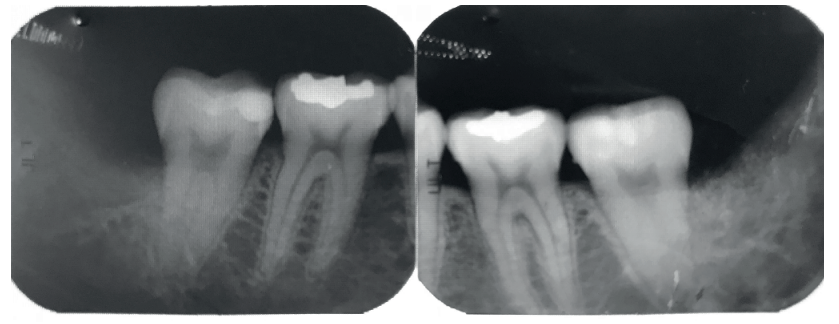

Se retiró la sutura de nuevo a la semana, y se realizaron revisiones a los 3 y 6 meses, donde se midió la profundidad de sondaje (Tabla). Se realizaron radiografías periapicales a los 3 meses (Figura 9) y a los 6 meses (Figura 10).

A los 6 meses se realizó una tomografía computarizada de haz cónico (Figura 11), para calcular la densidad ósea en el lado control (1372,33 Unidades Hounsfield) respecto al lado de estudio (1602,33 Unidades Hounsfield). Además, se comparó la altura a la cresta ósea en el lado control (disminución de 2,1 mm de altura ósea) respecto al lado de estudio (disminución de 0,9 mm de altura ósea).